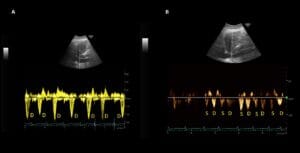

Interestingly, the patient lacked pedal edema or shortness of breath. A formal echocardiogram demonstrated reduction of left ventricular ejection fraction from a baseline of 37% to ~30%, new right ventricular enlargement with interventricular septal flattening (D-sign), and severe functional tricuspid regurgitation, suggestive of fluid overload (Figure 3). The patient history was not suggestive of pulmonary embolism. A nuclear medicine stress test was negative for ischemic changes. Over the subsequent three days, the nephrology team performed daily ultrafiltration, resulting in removal of 8 liters of fluid (net negative 4.5 liters on day 3). At the end of the second session, the nephrology team performed a follow up VExUS scan that showed significant improvement in the congestion. The portal vein was completely normalized, whereas the hepatic vein showed mild congestion with S-wave less than D-wave. A simultaneous ECG tracing was used to avoid errors in misidentification of the waves (Figure 4).

Figure 4. POCUS images demonstrating S<D pattern on hepatic vein Doppler and a normal appearing (pulsatility <30%) portal vein waveform.

The IVC maximal diameter improved to approximately 2.1 cm, with >50% inspiratory collapse with an estimated right atrial pressure of 8 mmHg (Figure 5). Follow up POCUS after the third session demonstrated further improvement in IVC size (<2 cm), and collapsibility consistent with an estimated right atrial pressure of 3 mmHg (Figure 6). Remarkably, the shape of the IVC shifted from circular to oval during the decongestion of the patient, which is a clinically useful qualitative parameter. Hepatic vein Doppler demonstrated further improvement in S-wave amplitude to near-normal configuration, and the portal vein remained continuous (Figure 7). Intrarenal venous Doppler was not performed, as it is unreliable in ESKD.

Figure 7. POCUS images demonstrating almost equal S and D waves on hepatic vein Doppler and a normal (pulsatility <30%) appearing portal vein waveform.